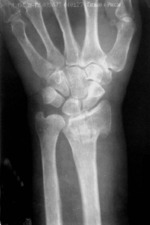

Дорогие мамочки! Подскажите, как быть...Вобщем прихожу вчера домой, старший мой уже дома... сразу стал жаловаться, что руку сильно ударил на тренировке по футболу. Он на воротах стоял, и когда мяч отбивал "руку назад вывернуло прям"... тренер отвёл в коридор, подержал руку под струёй воды и опять на ворота поставил... моему было больно, он заплакал, отпросился в медпункт, но там уже не было никого.. переоделся в кабинете и домой приехал... дома я наложила тугую повязку.. на утро рука опухла, когда папа отвёз его в травмпунк, оказалось перелом... перелом лучевой кости возле самой ладони.. когда папа сказал. что перелом произошёл в школе, ему ответили что им без разницы где... после больницы они с сыном заехали в школу... классный руководитель тоже сказала она не причём... я понимаю, что спорта без травм не бывает, но почему вот так всем всё равно, как и где пострадал ребёнок... теперь даже и не знаю, стоит ли к тренеру идти... правильно ли всё это.. у нас такая ситуация впервые... как-то погано на душе...